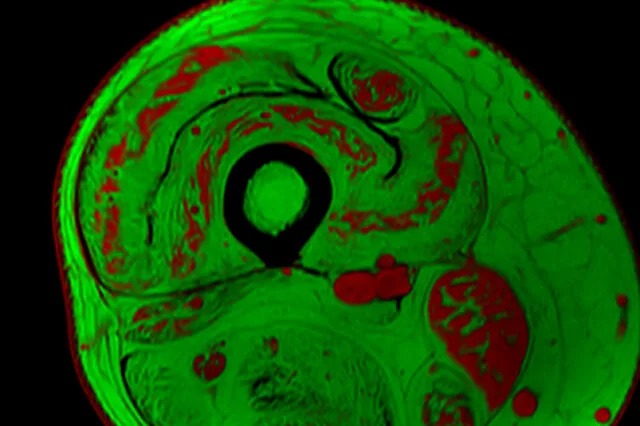

The new project is led by Dr. Krista Vandenborne, a distinguished professor and chair of the Department of Physical Therapy in the College of Public Health and Health Professions. Vandenborne pioneered the use of MRI biomarkers to capture highly accurate and noninvasive measures of muscle changes in children with Duchenne muscular dystrophy.

Neuromuscular diseases are emerging targets for experimental gene therapies that may stop disease progression. However, assessing the drugs’ effectiveness in clinical trials can be difficult, particularly if the results are determined based on measures of participants’ functions (such as walking speed or ability to climb stairs). Among young children, especially, these measures can be hard to obtain if the child is not highly motivated to participate in functional tests or is just having a bad day. Muscle imaging, on the other hand, provides objective and accurate evidence of muscle changes.